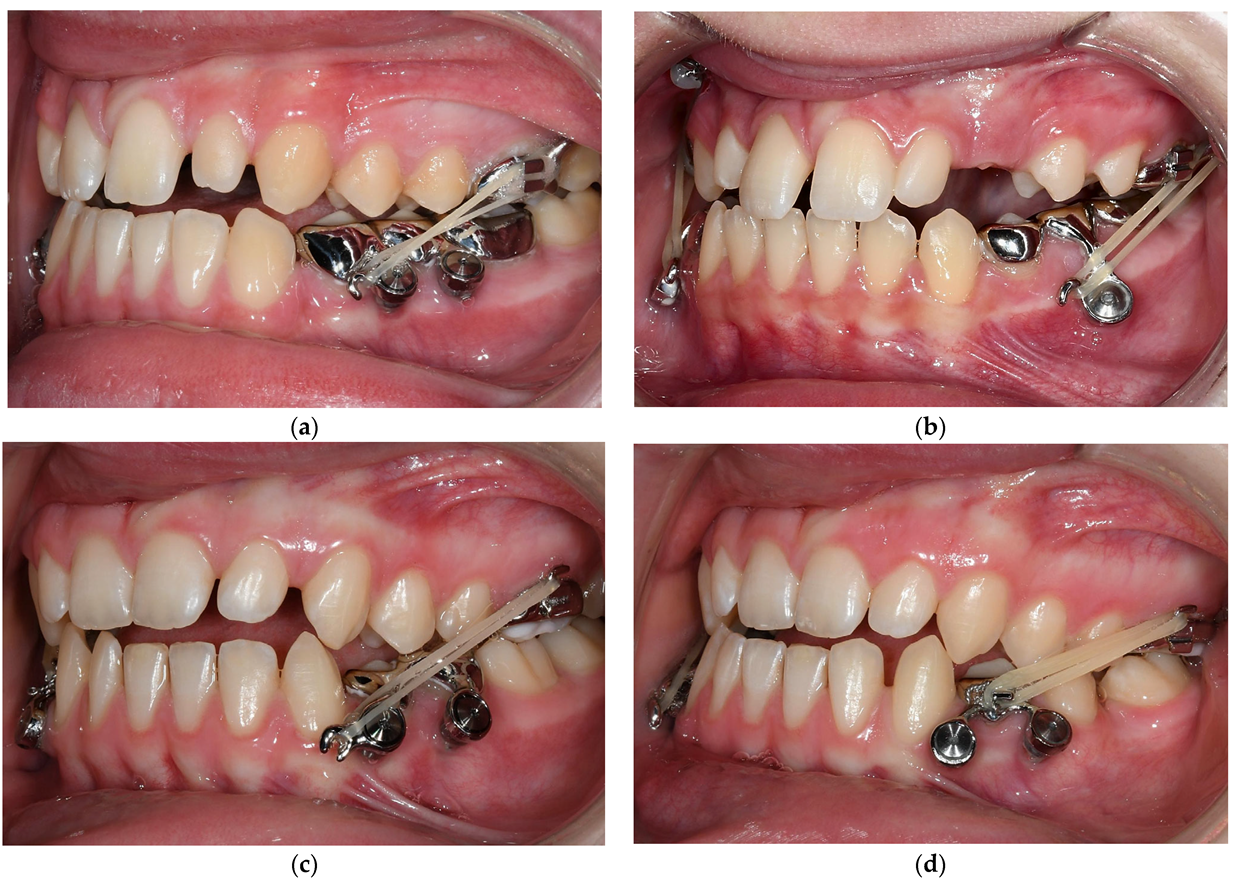

3.3. Treatment Progress

3.4. Treatment Results